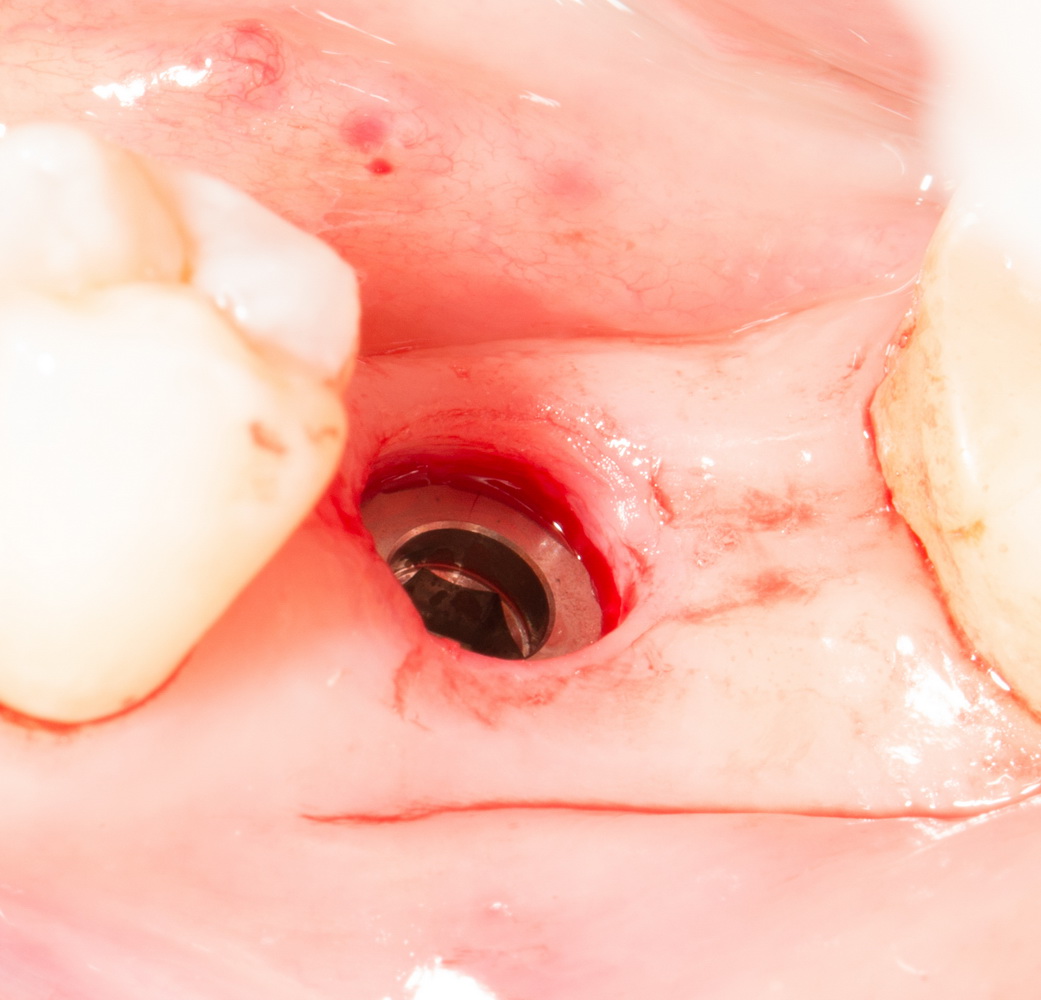

Лунка готова:

В данном случае мы используем XiVE, что, с одной стороны, несколько сложнее, чем, к примеру, использование погружного импланта, но, с другой — позволяет нам ориентироваться по абатменту TempBase, который входит в комплект поставки и является, одновременно, имплантодержателем:

Всё. Имплантат установлен:

Еще раз проверяем глубину погружения — с помощью зонда измеряем расстояние от импланта до поверхности слизистой оболочки — оно должно совпадать нашими замерами толщины десны. Ну и, проверяем, что имплантат со всех сторон окружен костной тканью: